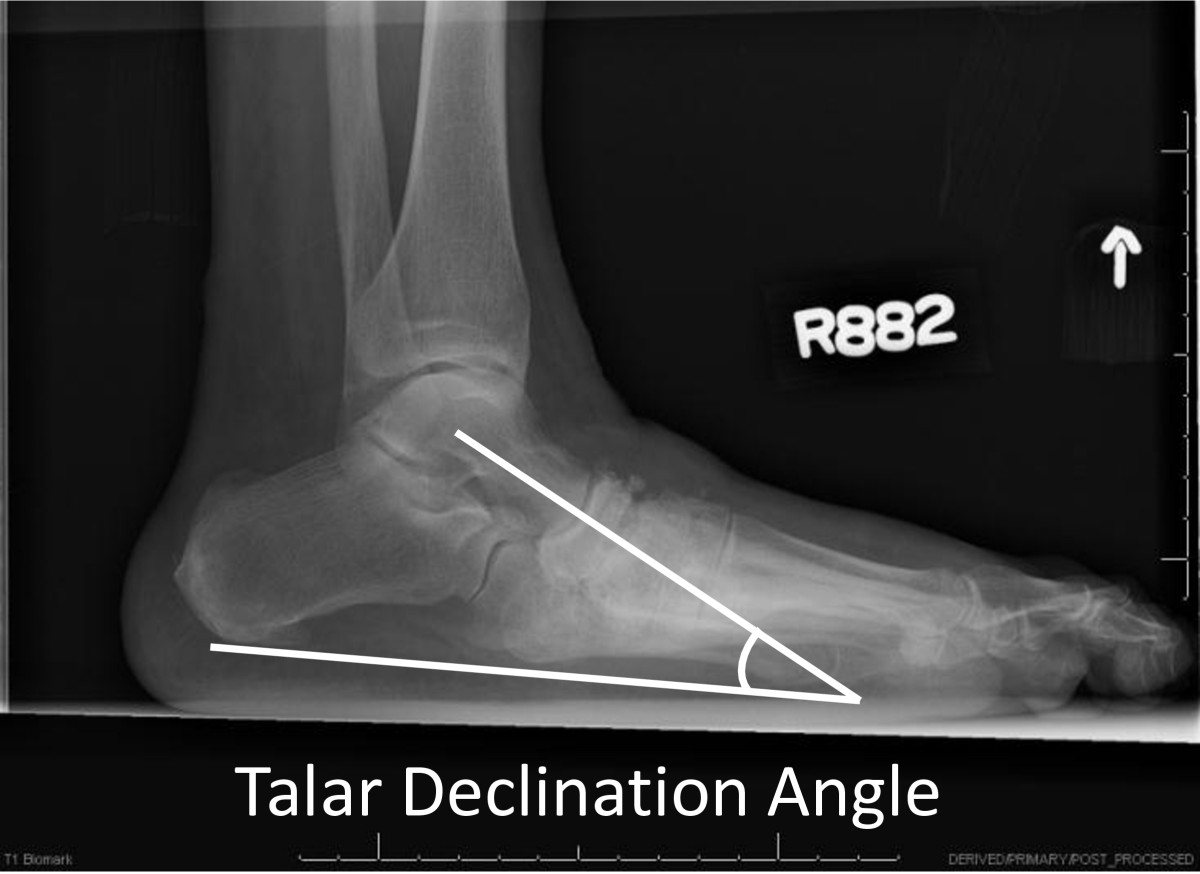

All participants had standardized weight-bearing radiographs of both feet (antero-posterior, lateral and oblique views). A research assistant monitored and standardized each foot position for image consistency and to minimize out-of-plane rotations [3]. A calibration ruler was included in each radiograph to calibrate each image and reduce geometric magnification errors. Radiographs were de-identified of all personal information then uploaded and imported into ISite PACS (Picture Archiving and Communication Systems) workstation software program for measurement (Philips Healthcare Informatics, Foster City, CA). The ISite PACS software measures angles to the nearest 1-degree increment. Talar declination and calcaneal inclination angles were assessed on the lateral view using the angle measurement function in the ISite PACS software. Standard view foot radiographs demonstrate single plane foot deformities. Talar declination and calcaneal inclination angles were selected to represent hind foot alignment changes in the sagittal plane that are best represented by the lateral view foot radiograph. The talar declination angle was measured as the angle formed between the collum tali axis, a line originating from the center of the body of the talus extended through the bisection of the talar neck and head with a horizontal line extending from the plantar surface of the calcaneus to the plantar surface of the 5th metatarsal head [21] (Figure 1). Talar declination angle was measured since it reflects the orientation of the distal head and neck of talus in the sagittal plane and is impaired in flat feet deformities [5]. Calcaneal inclination (pitch) angle was measured as the angle formed between lines extending from inferior portion of the calcaneocuboid joint to the same horizontal line along the plantar aspect of the calcaneus to the plantar surface of the 5th metatarsal head (Figure 2). Calcaneal inclination angle was measured since it reflects the orientation of the anterior calcaneus in the sagittal plane and is impaired in flat feet. The same rater performed radiographic measurements. As reported previously, measurement error as the standard deviation between repeat measurements is 2 degrees for both talar declination angle and calcaneal inclination angles in women 40 to 60 years of age [22]. Hastings et al. recently reported the intra-rater measurement precision of radiographic measures expressed as the root mean square standard deviation (RMS-SD) in participants with DM and PN and foot deformity is 2 to 3 degrees [23]. Both angle measures have been used to describe the alignment of the hind foot bones in the sagittal plane and reflect mid tarsal joint (talonavicular and calcaneocuboid) alignment in acquired neuropathic midfoot deformities [3, 5].

Figure 1

Talar declination angle formed by the line representing the collum tali axis through the head and neck of the talus and a line representing the weight bearing plantar surface from the calcaneus to the 5th metatarsal.